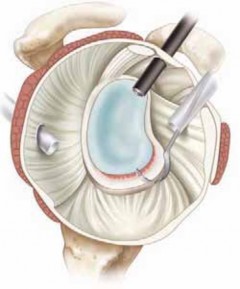

Patient positioning in the operating room is a matter of surgeon preference, with both the beach chair and lateral decubitus positions offering distinct advantages. The lateral decubitus position, utilizing 10 to 15 pounds of balanced suspension traction, provides unparalleled joint distraction, expanding the axillary pouch and facilitating excellent visualization of the inferior glenoid and IGHL complex. This position is highly advantageous for complex capsular shifts and inferior anchor placement. Conversely, the beach chair position offers a more anatomic orientation of the shoulder girdle, facilitates seamless conversion to an open procedure if necessary, and eliminates the risk of traction-related neurapraxia. Regardless of the chosen position, a thorough Examination Under Anesthesia (EUA) is mandatory prior to prepping and draping. The EUA allows the surgeon to assess the true magnitude of translation without muscle guarding, confirming the operative plan and identifying any unrecognized multidirectional components.

Following the diagnostic sweep, two anterior working portals are established using an outside-in spinal needle localization technique. The anterosuperior portal is typically placed just anterior to the acromioclavicular joint, entering the joint through the rotator interval superior to the biceps tendon; this serves primarily for fluid management and suture retrieval. The critical anteroinferior working portal is placed just superior to the upper border of the subscapularis tendon, ensuring an optimal trajectory (approximately 45 degrees to the glenoid face) for anchor insertion along the anteroinferior glenoid rim. A clear cannula (typically 5.5 mm or 8.25 mm) is introduced to facilitate smooth instrument passage and suture management.

Anchor Placement and Capsulolabral Plication

With the glenoid prepared and the tissue mobilized, fixation begins at the most inferior aspect of the lesion, typically at the 5:30 or 6 o'clock position. Modern fixation relies on either biocomposite or all-suture anchors, typically 1.5 mm to 2.9 mm in diameter. The drill guide is introduced through the anteroinferior portal, and the anchor is deployed on the articular margin (1-2 mm onto the articular cartilage face) to recreate the anatomical labral bumper. The trajectory of the drill is paramount; it must be directed slightly medially to avoid penetrating the articular surface of the glenoid vault.